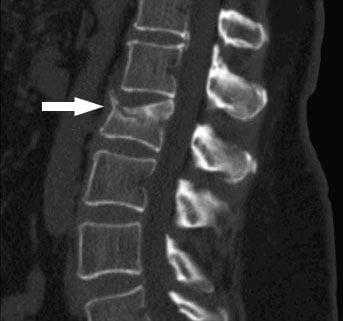

Баллонная кифопластика целесообразна только в случае недавнего компрессионного перелома, пока костные фрагменты не успели срастись в порочном положении. Специалисты предупреждают, что «возраст» вертебрального остеопоротического перелома, обусловившего кифоз, не должен превышать 8 недель. Тогда есть все шансы максимально полно восстановить анатомическое положение, форму и единство позвонка при помощи баллонной кифопластики. Обращаем внимание, что это миниинвазивное вмешательство, проведенное своевременно, оказывает мощное профилактическое действие против посттравматического кифоза. А осложнение в виде кифоза в любом случае намного проще предупредить. Как проходит процесс хирургического лечения, мы рассказывали в предыдущей части статьи.

Компрессионный перелом на срезе МРТ.

Но есть одна проблема, препятствующая использованию кифопластики, в том числе и вертебропластки. При остеопорозных переломах, зачастую возникающих спонтанно и с неинтенсивной симптоматикой, пациент не спешит с визитом в медучреждение, и терапия не осуществляется годами. Еще один момент, при обращении пациента в больницу, даже с жалобами на сильную боль в спине, не каждый специалист ставит верный диагноз.

Как результат, ввиду отсутствия целенаправленных лечебных действий на раннем сроке или по причине диагностической ошибки, когда лечат совсем не ту патологию, на уровне травмы деформированный сегмент в итоге самопроизвольно фиксируется ригидным костным блоком. Стеноз, нарастающий неврологический дефицит, прогрессирующая функциональная несостоятельность позвоночника - естественное дело для такого клинического случая. К сожалению, при очень грубых и застарелых клиновидных искривлениях кифопластика бессильна. Их исправляют уже только радикально: делается корригирующая вертебротомия в комбинации со стабилизацией остеосинтезом, спондилодезом, эндофиксаторами.